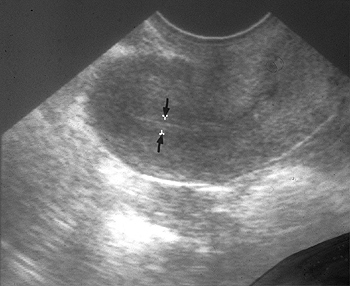

인공수정 시술에서 자궁내막의 두께와 임신율과의 상관 관계